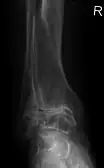

Diagnosis is made with reasonable certainty based on history and clinical examination.[42][43] X-rays may confirm the diagnosis. The typical changes seen on X-ray include: joint space narrowing, subchondral sclerosis (increased bone formation around the joint), subchondral cyst formation, and osteophytes.[44] Plain films may not correlate with the findings on physical examination or with the degree of pain.[45] Usually other imaging techniques are not necessary to clinically diagnose osteoarthritis.

Primary osteoarthritis of the left knee. Note the osteophytes, narrowing of the joint space (arrow), and increased subchondral bone density (arrow). -